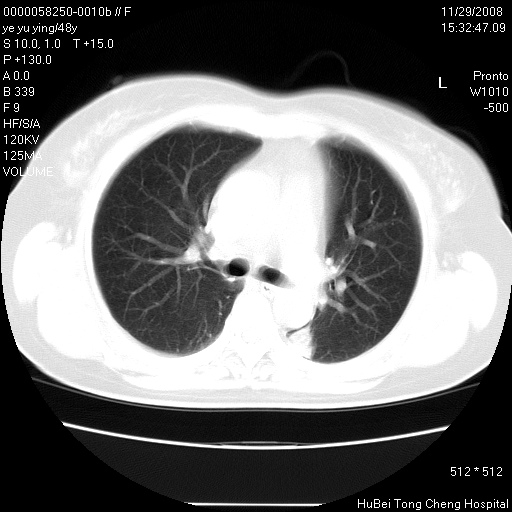

以下是引用huenhao在2008-11-29 22:11:00的发言:[br]脂肪肝,胆囊结石。左肺病灶建议定期复查。

以下是引用liuyue在2008-11-30 5:44:00的发言:[br]1.左肺病变,首先考虑感染性病变,转移待排;建议治疗后复查。[br]2.肝脏密度普遍减低,考虑与化疗有关。[br]3.胆囊结石.